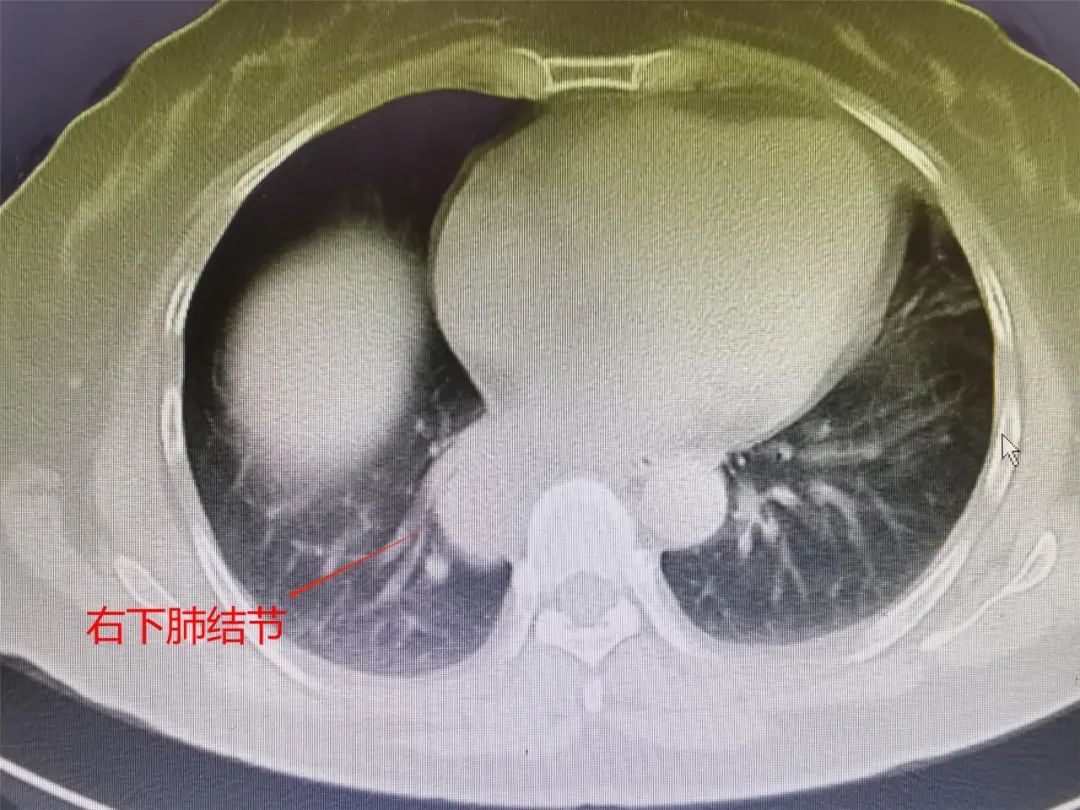

趙大媽1年前在我院行直腸癌微創(chuàng)手術(shù)及術(shù)后化療,此次復(fù)查胸部CT增強(qiáng)提示新發(fā)右縱隔或右下肺腫物約3.2×2.5cm,單孔胸腔鏡下探查后確診為右下肺癌,考慮原發(fā)可能。胸外科團(tuán)隊(duì)認(rèn)真分析了患者具體病情,結(jié)合術(shù)中詳細(xì)評(píng)估,制定了最優(yōu)化的手術(shù)方案,給予行單孔胸腔鏡下根治性右下肺葉切除術(shù),術(shù)中冰凍提示非小細(xì)胞肺癌。

CT影像&病理診斷